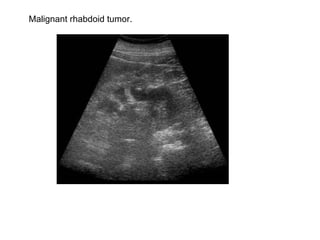

Malignant rhabdoid tumor.